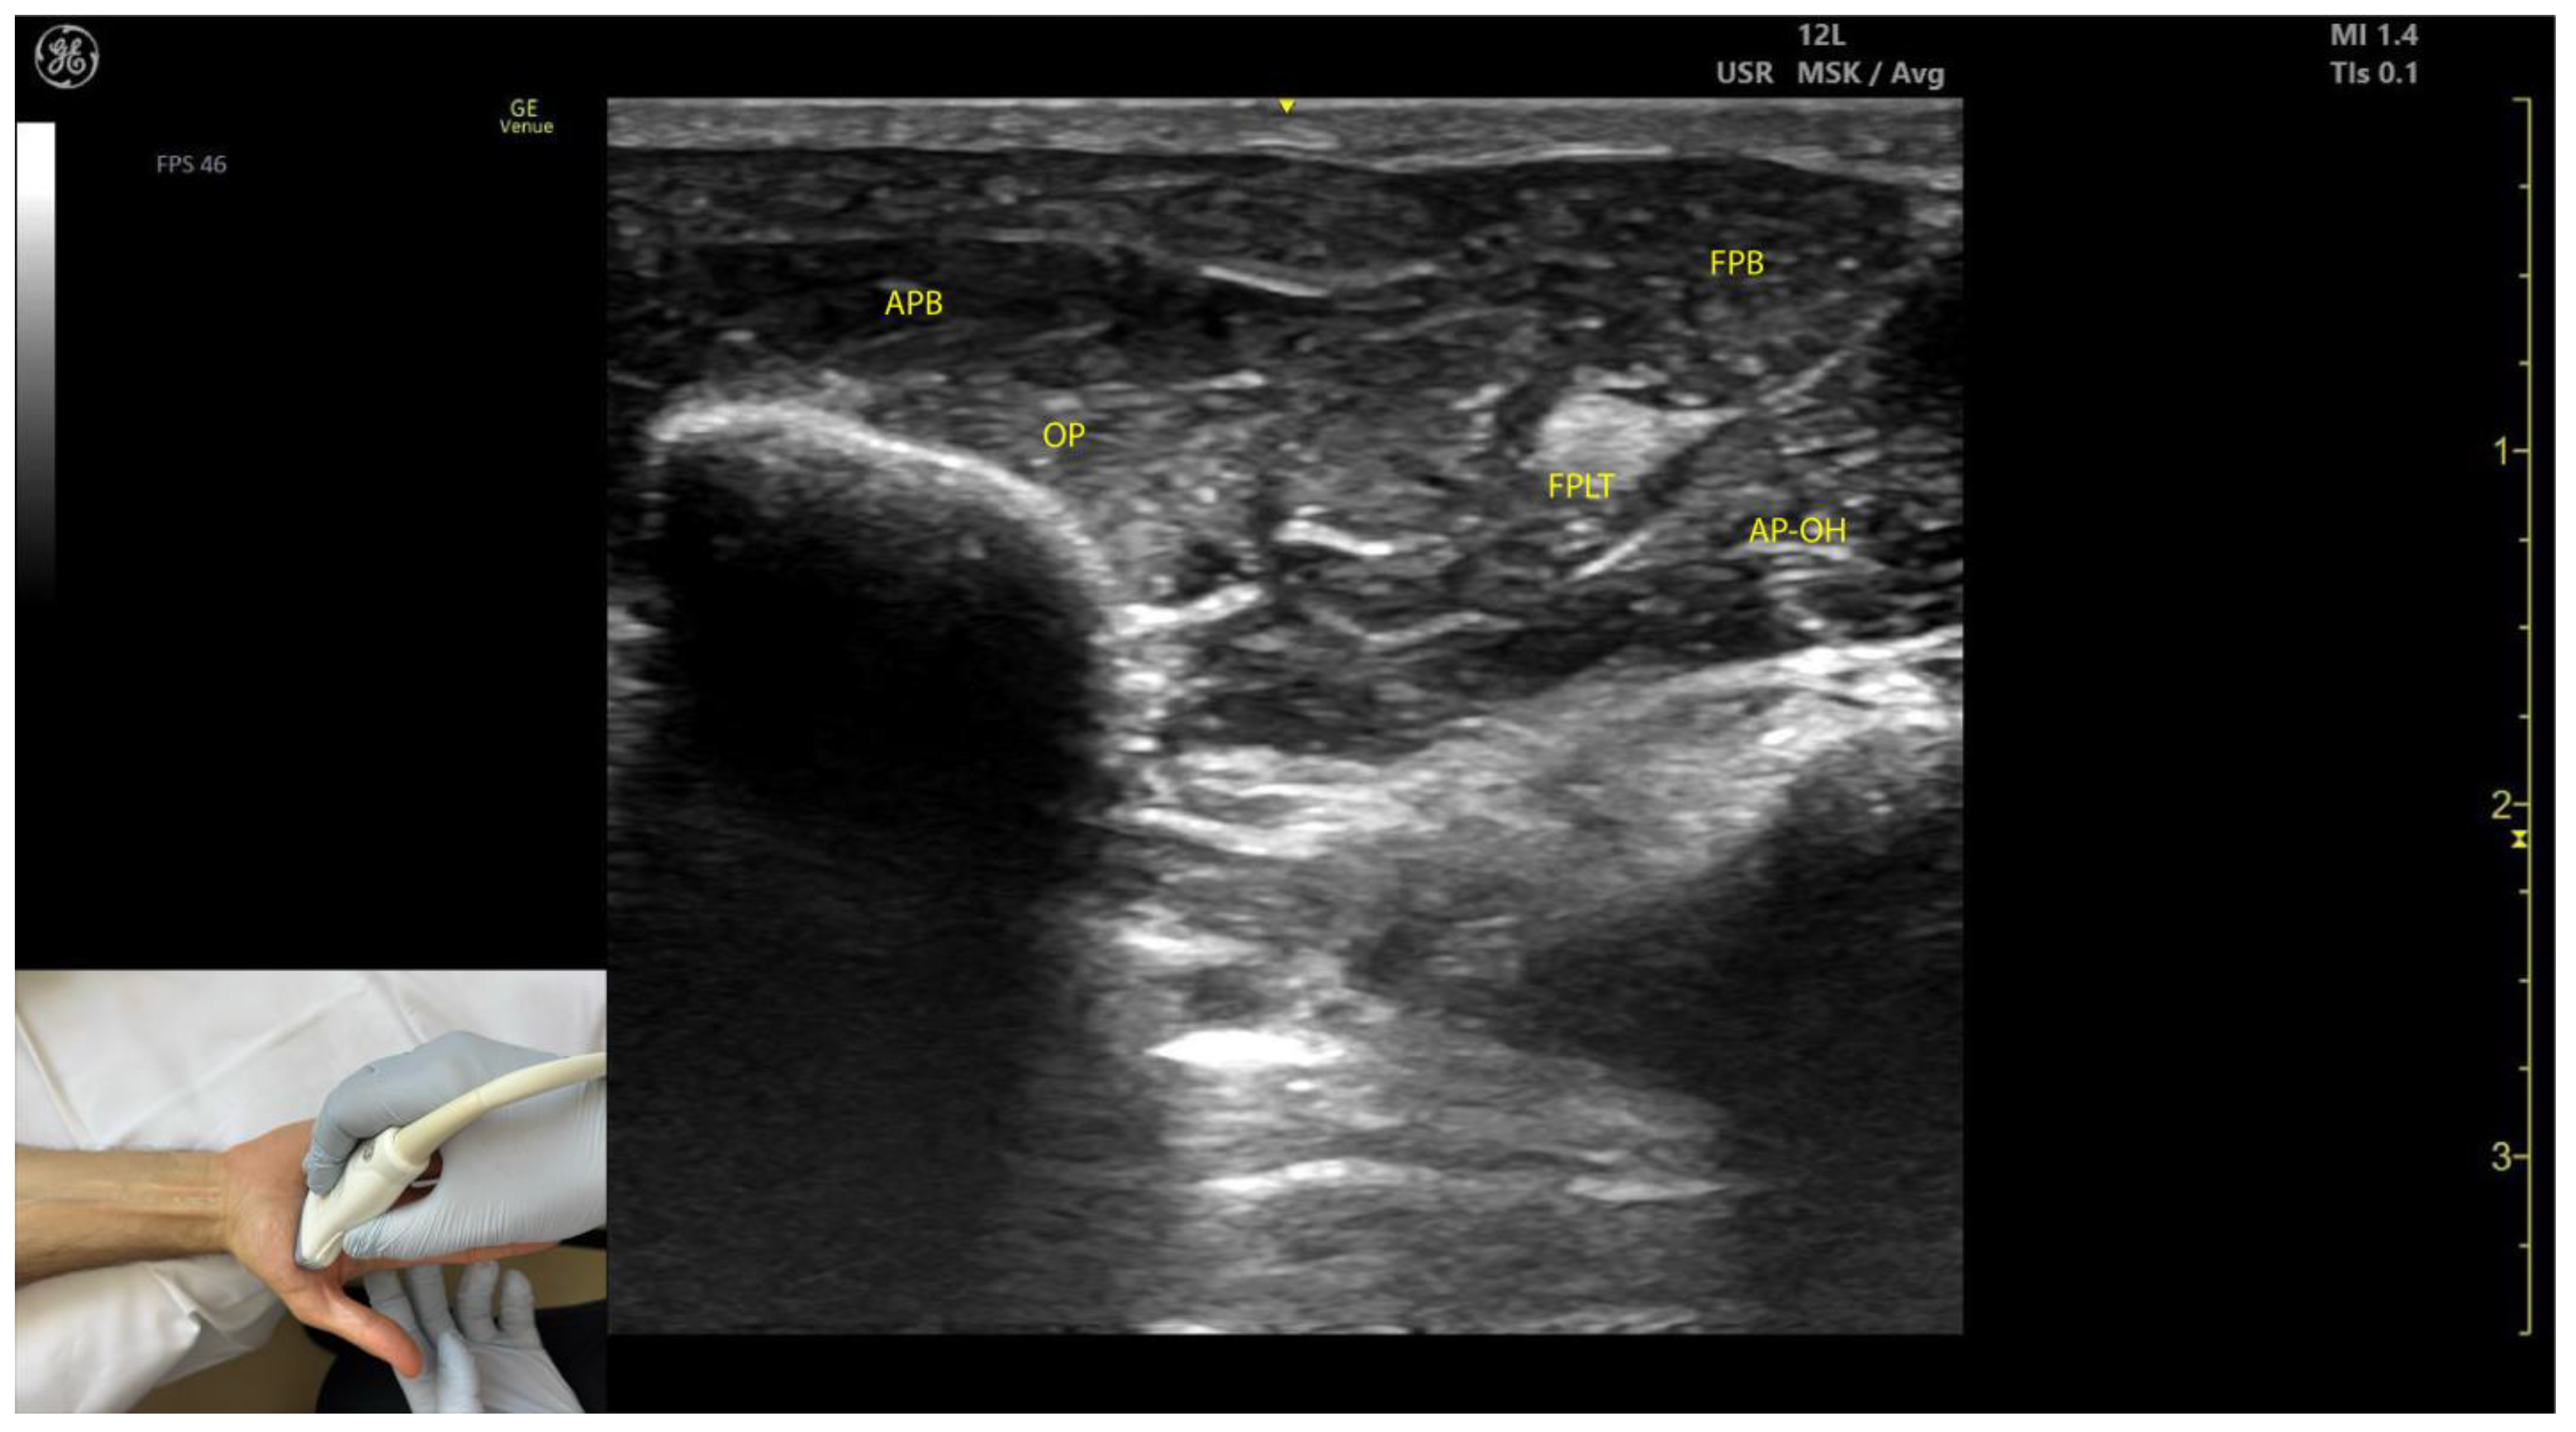

2.8.3. Key Ultrasound Landmarks (Figure 8)

- Muscle position: The APB is the first muscle mass from lateral to medial within the thenar eminence, also being the most superficial muscle mass of the thenar eminence [49].

- External fascia: The APB muscle lacks a pronounced fascia to clearly separate it from adjacent muscle masses, such as the opponens pollicis and flexor pollicis brevis, which can complicate precise localization during BoNT-A injections.

2.8.4. Clinical Implications and Injection Strategy

- The region with the highest density of intramuscular nerve arborizations of the APB is located 40% along the line connecting the hook of hamate to the head of the first metacarpal [51].

- In our clinical practice, the APB is targeted for BoNT-A injections at the point of maximum muscle thickness, determined via ultrasound, typically located at the base of the thenar eminence.

2.9. Opponens Pollicis (OP)

2.9.1. Overview

2.9.2. Ultrasound Identification

2.9.3. Key Ultrasound Landmarks (Figure 8)

- Muscle position: The OP is the second structure from superficial to deep within the thenar eminence [52].

- Muscle size: It is the largest muscle within the thenar eminence [53].

- Lateral position: The OP is located lateral to the flexor pollicis brevis (FPB) [53].

- External fascia: The OP muscle lacks a pronounced fascia to distinctly separate it from adjacent muscle masses, such as the abductor pollicis brevis and flexor pollicis brevis, which may make precise localization during BoNT-A injections more challenging.

- Dynamic evaluation: Scanning distally toward the MCP joint shows an increase in the size of the OP and a corresponding decrease in the size of the APB. At this level, the tendon of the FPL can be seen deep to the OP [54]. Muscle contraction of the OP is observed during adduction and medial rotation of the thumb at the CMC joint, flexion at the MCP joint, or during thumb opposition when the tip of the thumb contacts the fifth finger [55].

2.9.4. Clinical Implications and Injection Strategy

- The region with the highest density of intramuscular nerve arborizations of the opponens is located 60% along the line connecting the hook of hamate to the head of the first metacarpal [51].

- In our clinical practice, BoNT-A injections into the OP are performed at the point of maximum muscle thickness, as determined by ultrasound. The optimal injection site is typically located approximately 1 cm proximal to the MCP joint on the palmar aspect of the hand. Ultrasound guidance ensures accurate delivery while avoiding adjacent structures, such as the flexor pollicis longus tendon.